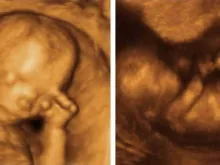

O que um nascituro experimenta no ventre materno?

Atualmente, difundiram a posição pró-aborto na qual o nascituro não deve ser considerado um ser humano, caso não seja capaz... Leia mais